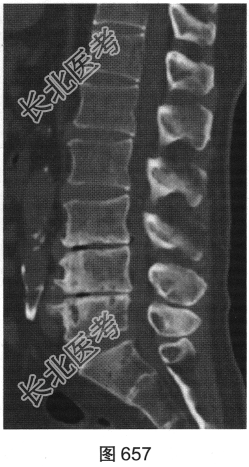

- 多项选择题2.[提示]患者行腰椎X线及CT检查,见图655~图659。患者有哪些阳性影像学表现( )

A、椎间盘“真空现象”

B、腰椎前滑脱

C、椎间盘膨出、突出

D、腰椎轻度侧弯

E、椎小关节骨质增生硬化

F、腰椎间隙变窄